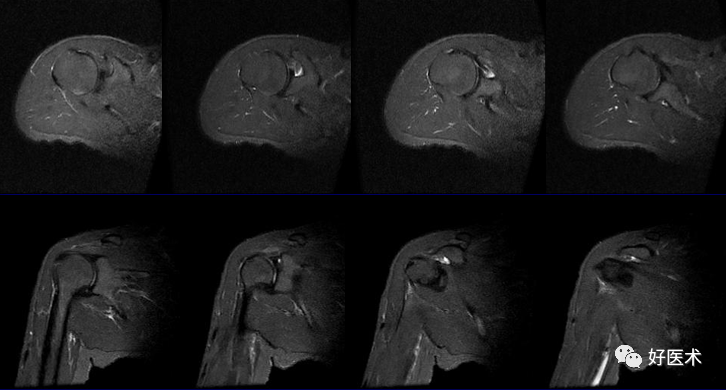

MRI检查技术

(1)体位

-

仰卧位:检查侧上肢紧贴身体呈中立位或轻度外旋位。

ABER位(前臂外旋外展位):检出关节盂及韧带病变

(2)扫描方位

横轴位:取三维立体定位像的冠状像,扫描层面与关节盂垂直,扫描范围从肩峰至肱骨颈下。

斜冠状位:取横断位作定位像,扫描层面与冈上肌腱平行,扫描范围为锁骨外端至肩峰。

斜矢状位:取横断位作定位像,扫描层面与关节盂平行,扫描范围包括肱骨头和整个关节盂。

轴位:评估Bankart lesions 和盂唇损伤、评估肩胛下肌肌腱。

斜冠状、斜矢状:显示肩袖及冈上肌走行、显示喙肩弓。

斜冠状、轴位:评估盂唇撕裂、肱二头肌长头腱与上盂唇的连接。

轴位:显示肩胛下肌腱撕裂、盂唇撕裂

冠状位:显示肩袖撕裂、盂唇撕裂

矢状位:显示肩袖撕裂、盂唇撕裂